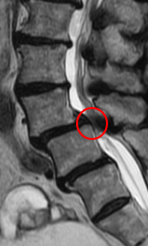

この患者様は赤い枠で示されている箇所(L4/5)に脊柱管狭窄症、すべり症が認められ、特にL4/5脊柱管狭窄症に強く狭窄を認めました。